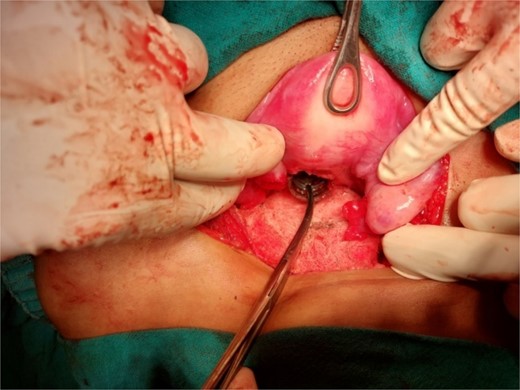

A 26-year-old nulliparous lady from a rural area was referred to emergency from a primary health care centre with a failed attempt to remove an impacted uterine foreign body. On per speculum examination, an impacted hard pipe-like structure was protruding from the cervix. The patient gave a history of foreign body insertion 9 years back, however, failed to provide a detailed account of the mode of insertion or history of sexual assault. She went to seek medical care only after developing profuse foul-smelling discharge and chronic pelvic pain. Removal was attempted under local anaesthesia but failed. Transvaginal scan showed a bulky uterus with an apparently normal endometrial thickness and echotexture; however, the cervical canal was distended with an echogenic area and areas of calcification (Figs 1 and 2). She was taken up for removal of the foreign body under general anaesthesia. As a hard pipe-like structure was already protruding, removal was tried by grasping it with a Kocher’s forceps. After multiple attempts part of the foreign body was removed. Hysteroscopy showed that the lower endocervical canal was clear and a ring-like structure occupied the upper endocervical canal. Removal under direct vision using a hysteroscopic grasper was attempted but failed due to the impaction and size of the object and the hysteroscope could not be negotiated beyond the object. A laparotomy was performed and after an assessment of anatomy and tactile sensation to assess accessibility, incision on the posterior surface of the uterus was given (Figs 3 and 4) and the object was removed (Fig. 5). The incision was closed in two layers. Intercede was placed at the repair site. An extended course of antibiotics was given for 7 days. Post-operative recovery was uneventful. Contraception for at least 1 year, the need for proper antenatal care, the risk of rupture, and mandatory caesarean delivery were counselled to the couple.

Extraction of the foreign body through a posterior hysterotomy incision.

The perfume nozzle head retrieved from posterior hysterotomy and the nozzle with ring and spring removed vaginally.